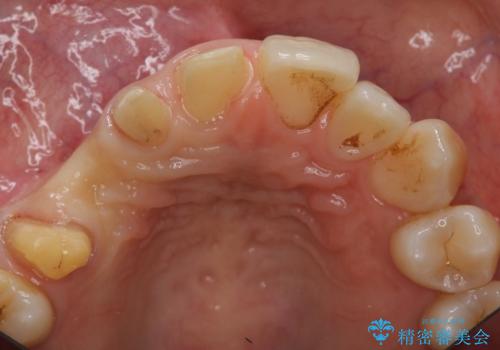

- 右上の歯はもともとなかったが、ブリッジにするのが嫌でプラスチックの歯を応急的に接着剤でつけていたのがとれてしまったとのことでした。

接着剤で留めてある周りが、虫歯になってしまっていました。

しっかり虫歯を取ったうえで、清掃性の高いブリッジにしていくことをおすすめしました。

右上④3②①ブリッジの設計としました。